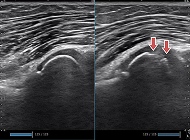

肉離れ

(腓腹筋)

診断だけでなく、治癒過程も評価できます。

アキレス腱断裂

診断だけでなく、動的評価、治癒過程も評価できます。